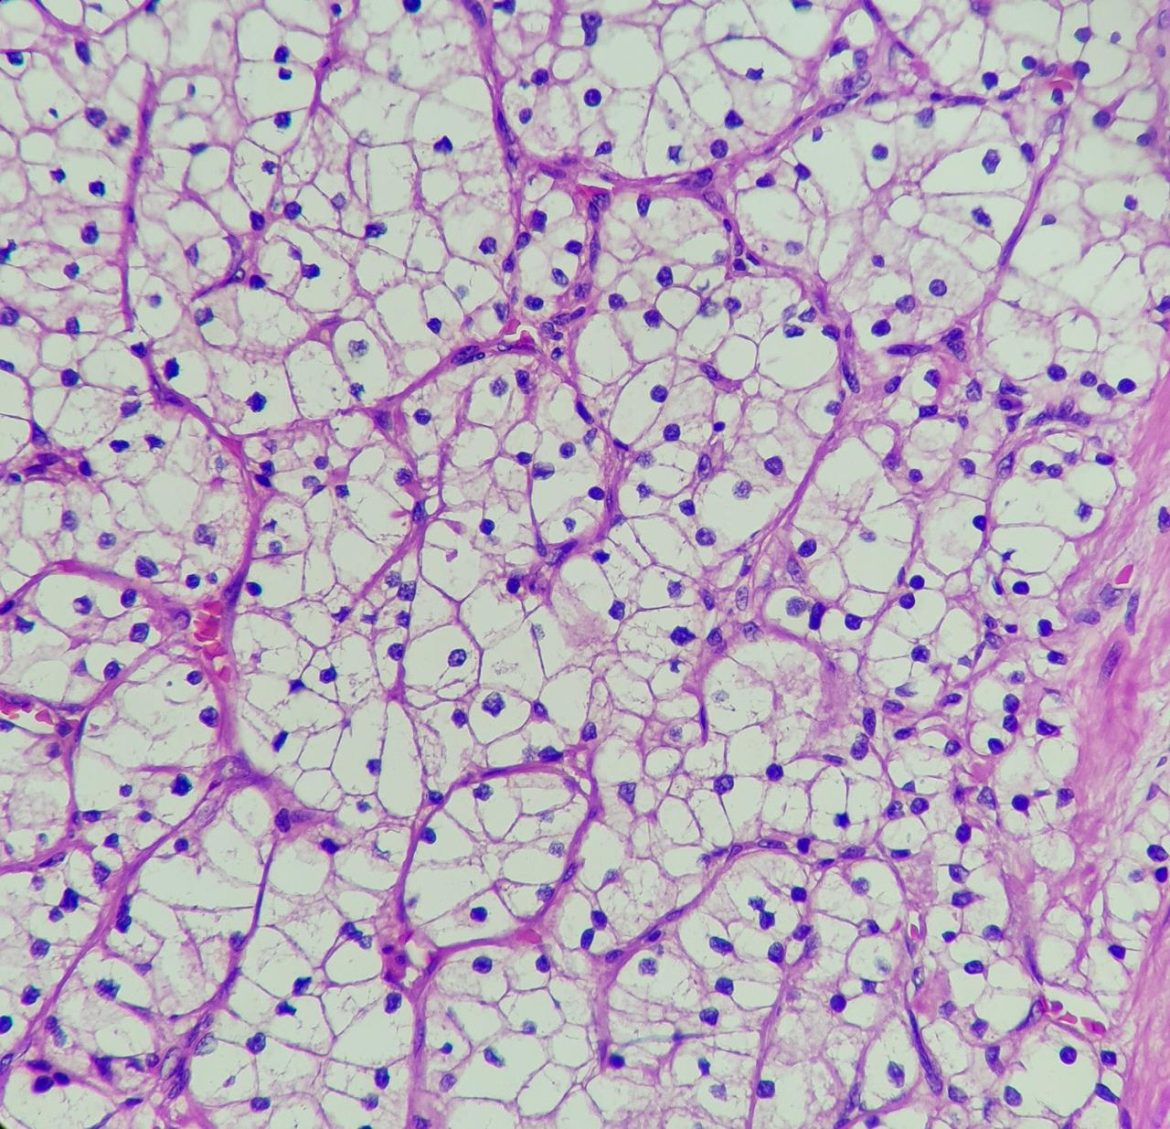

Roma, 12 feb. (Adnkronos Salute) – Nei pazienti con carcinoma a cellule renali avanzato (aRcc) non precedentemente trattato, cabozantinib (inibitore della tirosin chinarsi, Tki) in associazione a nivolumab, rispetto a sunitinib, per oltre 5 anni, ha mostrato un’efficacia superiore aumentando la sopravvivenza e prolungando il tempo alla progressione del tumore, indipendentemente dalla classificazione del rischio basata sui punteggi dell’International Metastatic Renal Cell Carcinoma Database Consortium. Sono i risultati finali dello studio di fase 3 CheckMate 9ER che – informa Ipsen – saranno presentati da Robert J. Motzer durante l’American Society of Clinical Oncology Genitourinary Symposium (Asco Gu) in programma dal 13 al 15 febbraio 2025 a San Francisco, California (Abstract #439).Con un follow-up mediano di 67,6 mesi per la sopravvivenza globale (Os) – riporta una nota – lo studio ha dimostrato che i benefici iniziali di sopravvivenza della combinazione cabozantinib e nivolumab si sono mantenuti rispetto a sunitinib, con un incremento assoluto mediano dell’Os di 11,0 mesi (46,5 mesi per la combinazione vs 35,5 mesi per sunitinib, rapporto di rischio (Hr) 0,79, intervallo di confidenza (Ci) 95%: 0,65-0,96. Inoltre, la combinazione ha dimostrato una riduzione del 42% del rischio di progressione di malattia o di morte, con una sopravvivenza libera da progressione mediana raddoppiata per la combinazione rispetto a sunitinib, 16,4 vs 8,3 mesi rispettivamente (Hr 0,58; 95% Ci: 0,49-0,70). Il profilo di sicurezza è risultato in linea con quelli già noti dei singoli farmaci, con eventi avversi correlati al trattamento che si sono verificati nel 98% dei pazienti trattati con la combinazione rispetto al 93% di quelli trattati con sunitinib. Non sono emerse nuove segnalazioni di sicurezza.”Nell’ultimo anno sono state stimate oltre 13mila nuove diagnosi di carcinoma renale in Italia, un numero ancora molto elevato e che sottolinea la necessità di trovare opzioni terapeutiche sempre più innovative, in grado di cambiare il corso di questa neoplasia – afferma Chiara Marchesi, Medical & Regulatory Affairs Director Ipsen Italia – I risultati dello studio CheckMate 9ER hanno contribuito in modo significativo alla trasformazione del panorama terapeutico del carcinoma a cellule renali negli ultimi anni. La combinazione di cabozantinib e nivolumab sta dimostrando significativi benefici a lungo termine per più di cinque anni, confermandosi così un trattamento standard che permette ai pazienti una maggiore sopravvivenza”.Nel 2022 sono stati diagnosticati più di 400mila nuovi casi di tumore del rene a livello globale. Tra questi, il carcinoma a cellule renali (Rcc) è il tipo più comune di tumore del rene (circa il 90% dei casi). E’ quasi 2 volte più comune negli uomini e i decessi dei pazienti maschi rappresentano oltre i due terzi. L’Rcc in stadio iniziale spesso non presenta sintomi distintivi, il che porta il 30% delle persone a ricevere la diagnosi in una fase avanzata di malattia. Tra i pazienti con Rcc avanzato, il 60% non riceve un trattamento di seconda linea. Se diagnosticato in stadi iniziali, il tasso di sopravvivenza a 5 anni è elevato, ma nei pazienti con Rcc metastatico in stadio avanzato il tasso di sopravvivenza è decisamente più basso, intorno al 17%.”Il 60% dei pazienti con carcinoma a cellule renali avanzato – sottolinea Camillo Porta, oncologo medico e professore all’Università di Bari ‘A. Moro’ – non arriva alla terapia di seconda linea: questo dato sottolinea l’importanza di assicurare le cure più efficaci il prima possibile. Il fatto di poter contare su un’unica chance di trattamento per così tanti pazienti rende i risultati finali di CheckMate 9ER davvero rilevanti per la pratica clinica quotidiana. Infatti, questi dati finali convalidano ulteriormente la possibilità di ottenere una sopravvivenza a lungo termine con cabozantinib e nivolumab a questo stato avanzato della malattia”.